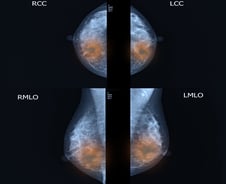

"혹시 유방암이면 어떡하지?" 어느 날 가슴에 찌릿한 느낌이나 통증이 느껴질 때 많은 여성이 유방암을 의심한다. 유방암은 국내 여성 암 가운데 가장 많이 발병하는데, 최근 발병 연령 범위가 커지고 있어 걱정하는 사람이 많다. 하지만 여성의 가슴 통증은 호르몬 변화, 생리 주기 등에 따라 나타났다가 사라지고 또다시 나타나는 경우가 더 많다. 이런 상황을 반복하면서 증상이 완화하면 '착각했나 보다'라고 여겨 넘기기에 십상이다. 민트병원 이선정 유방갑상선센터장(영상의학과 전문의)은 "유방암은 초기에 통증·증상이 거의 없어 정기검진을 통한 조기 발견이 중요하다"고 조언했다. 유방암의 대표적인 증상은 가슴에 만져지는 멍울(혹)이다. 유방에는 섬유선종과 같은 양성종양도 워낙 흔하게 발생해 악성종양(유방암)과 감별해야 한다. 다만 초기 유방암에서는 멍울이 거의 잡히지 않고, 정상조직(유선·피하지방)을 혹으로 오인할 수 있어 검사의 정확도가 중요하다. 유방암은 양성종양보다 딱딱하고, 잘 움직이지